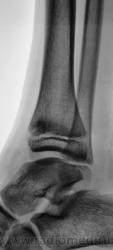

Травма. Пациент направлен хирургом на рентгенографию голеностопного сустава. Произведено стандартное исследование.

Уважаемый Валентин Львович! А что в жалобах, анамнезе? В переднемедиальной зоне дист. метафиза б/берцовой кости субхондрально под зоной роста участок уплотнения к/структуры, не отграниченный от неизмененной костн. ткани. Возможно, это импрессионный перелом? или остеонекроз? Смущает небольшой очаг аналогичной структуры в таранной кости под медиальным валом блока.

А, что, это за фрагментик?

1.Fragent.JPG2.Fragent.JPG3.Fragent.JPG

У взрослого такие соотношения в суставе назову супинационным подвывихом, хотя прямая проекция не оптимальна для такого заключения, боковая вовсе косая.

Алё, детские рентгенологи! Уплотнение костной структуры над зоной роста патологическое или нет?